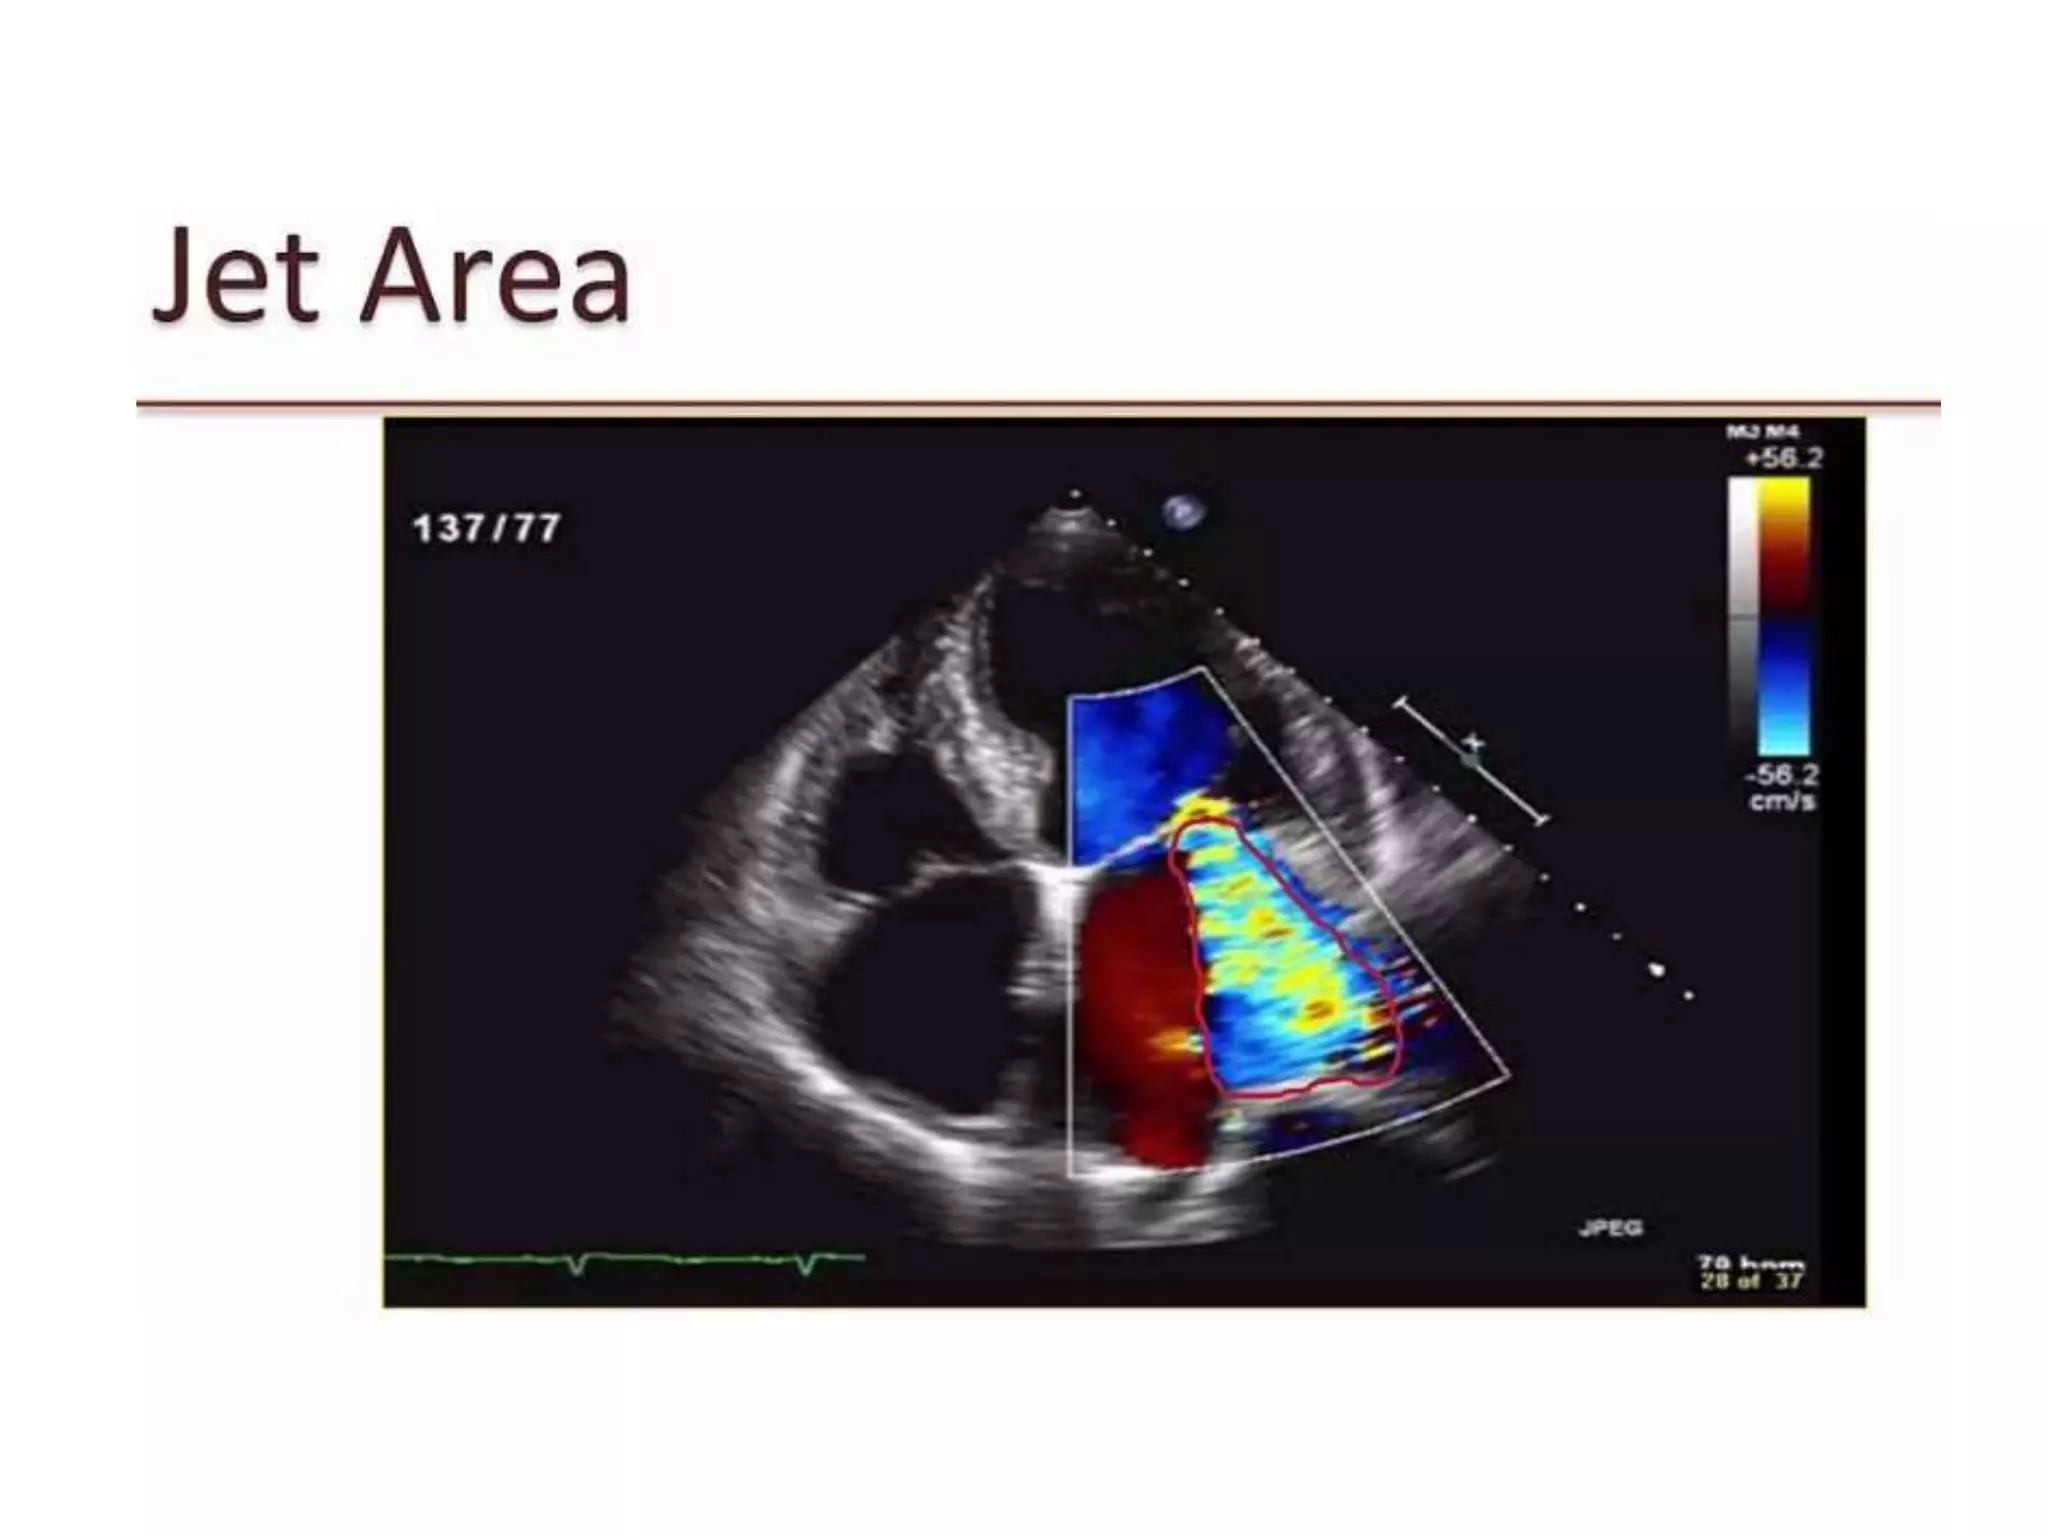

Mitral regurgitation is the abnormal reversal of blood from the left ventricle to the left atrium, caused by disruption of the mitral valve apparatus. It can be divided into acute, chronic compensated, and chronic decompensated stages. The etiology includes primary causes where the valve itself is abnormal, and secondary causes where the heart problem leads to valve dysfunction. Diagnosis is typically made using a 2D echocardiogram to visualize the valve and assess the severity and cause of regurgitation. Treatment options involve medical management or surgical repair or replacement of the valve.